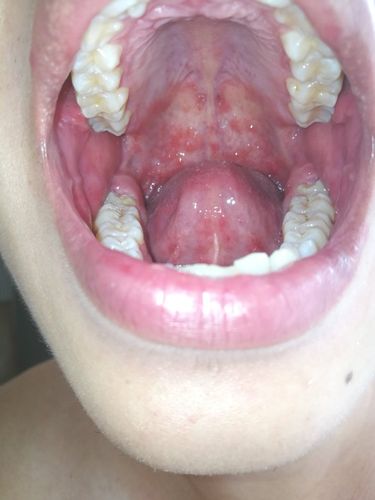

口腔上颚红点一定是艾滋吗?

口腔上颚红点”与艾滋病(HIV)的关系,这是一个需要非常严谨和科学态度来回答的问题。我必须首先强调:任何皮肤或黏膜上的症状都不能作为诊断艾滋病的依据。 自我诊断或仅凭图片判断是极其危险且不负责任的。

HIV急性期(感染后的2-4周)的口腔症状多种多样,上颚出现红点并非其典型或特异性的症状,将任何红点都怀疑为艾滋病,只会带来不必要的恐慌和焦虑。

(图片来源网络,侵删)- 表现:在急性期,由于全身免疫应激反应,口腔内任何部位(包括上颚)都可能偶尔出现单个或多个小的、疼痛的红点或溃疡。

- 特点:这与普通人压力大、上火、缺乏维生素时长的“口疮”非常相似,完全没有特异性。

艾滋病急性期极少以“上颚红点”为典型表现,如果您在上颚看到了红点,它更有可能是以下情况:

上颚出现红点、小红斑或小疙瘩,绝大多数情况下与艾滋病无关,而是由以下原因引起:

- 图片无法代表诊断:一张口腔上颚的红点图片,无论它是否来自HIV感染者,都无法作为诊断依据,同一个症状在不同人身上可能由完全不同的病因引起,仅凭图片进行判断是极不专业的,也是无效的。

- 个体差异巨大:HIV感染者的口腔表现千差万别,没有所谓的“标准图片”,而普通的上颚损伤也多种多样,两者在外观上极难区分,甚至可能完全一样。

口腔上颚的红点,绝大多数情况是物理刺激或普通炎症所致,与艾滋病无关,切勿依赖网络图片进行自我诊断,这只会徒增烦恼,如果您有高危行为,请务必通过专业的HIV检测来确认您的健康状况,这才是对自己和他人负责任的做法。